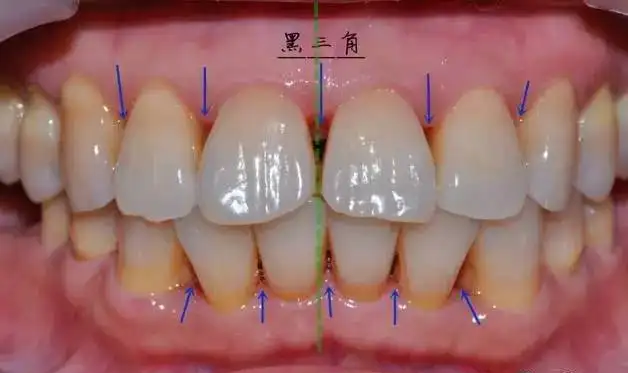

“牙龈线下移”,即牙龈萎缩,指的是牙根部位的牙龈退缩,将牙根暴露出来。牙龈萎缩不可小觑,如不重视,严重者会出现牙齿松动,甚至脱落。

一旦出现牙龈萎缩,表现为:牙龈红肿,刷牙出血;牙齿变长,牙缝变大;牙根开始暴露;遇到冷热酸甜,牙齿敏感;牙齿松动。